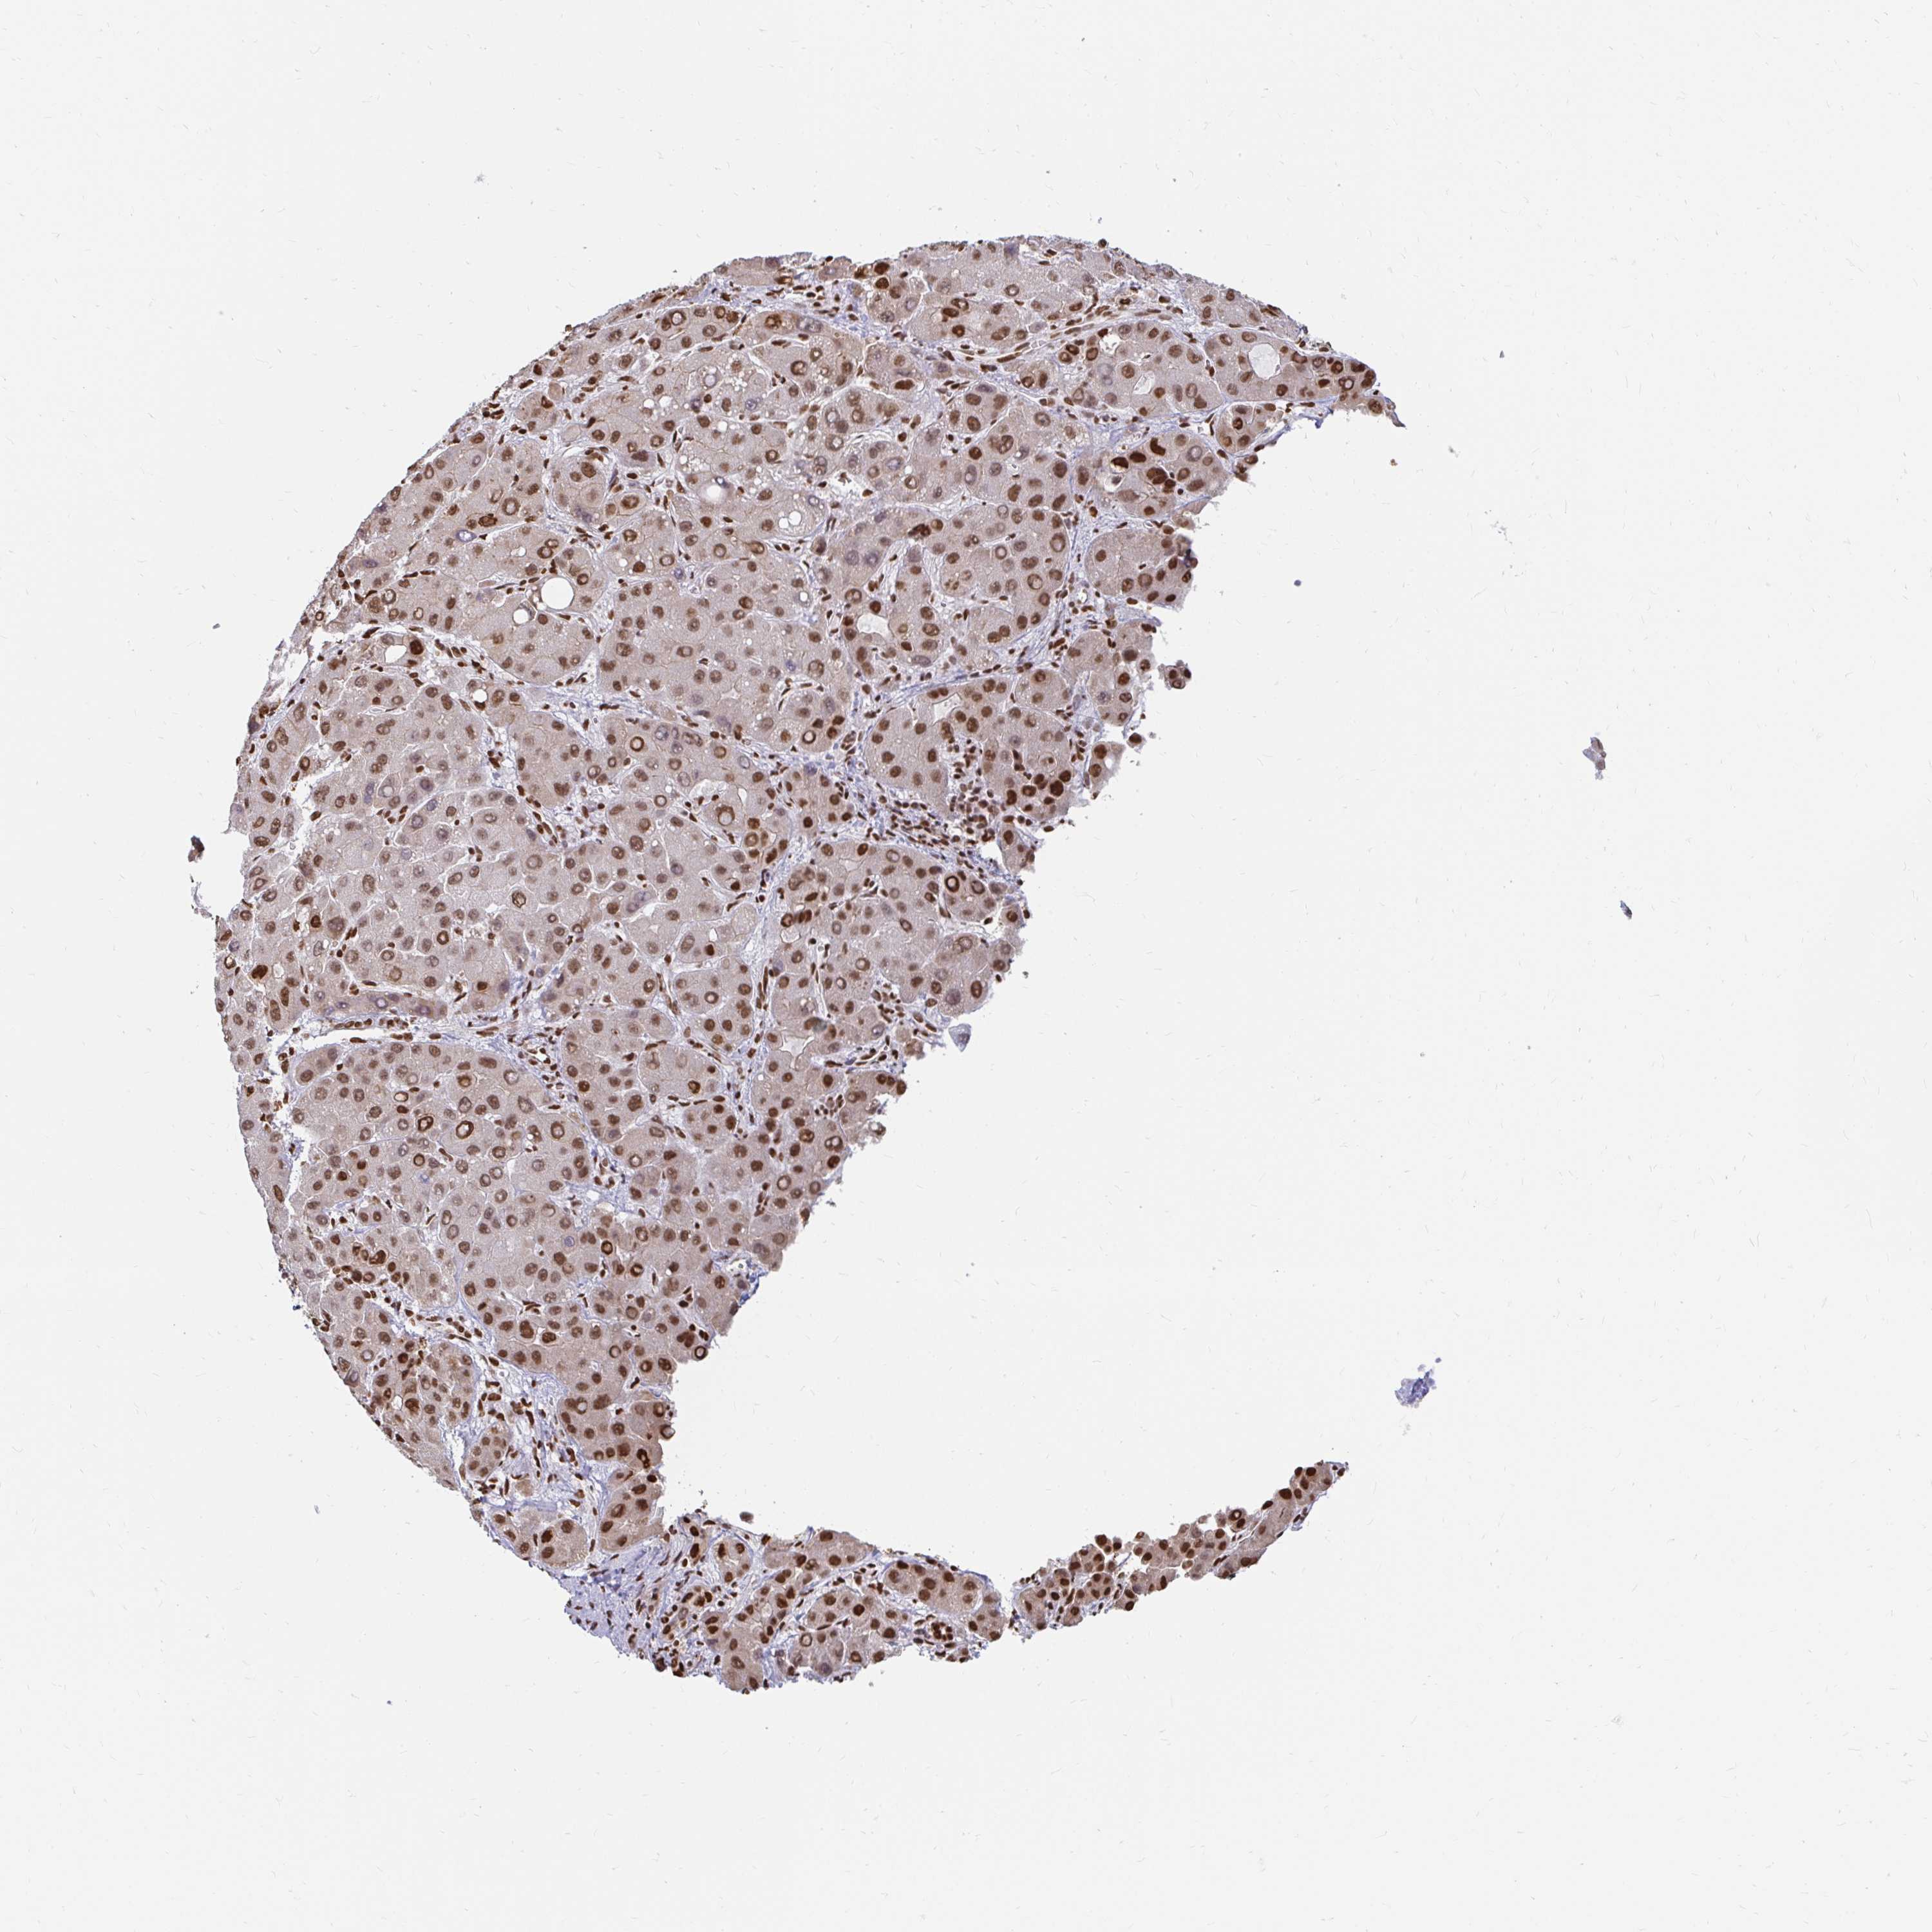

LIVER CANCER - Protein expressioni

A mouse-over function shows sample information and annotation data. Click on an image to view it in a full screen mode. Samples can be filtered based on level of antibody staining by selecting one or several of the following categories: high, medium, low and not detected. The assay and annotation is described here.

Note that samples used for immunohistochemistry by the Human Protein Atlas do not correspond to samples in the TCGA dataset.

Antibody stainingi

Antibody staining in the annotated cell types in the current human tissue is reported as not detected, low, medium, or high, based on conventional immunohistochemistry profiling in selected tissues. This score is based on the combination of the staining intensity and fraction of stained cells.

Each image is clickable and will lead to virtual microscopy that enables deeper exploration of all samples and also displays staining intensity scores, fraction scores and subcellular localization as well as patient and tissue information for each sample.

Antibody HPA041057

Antibody HPA058707

Antibody CAB011532

Staining

High

Medium

Low

Not detected

Intensity

Strong

Moderate

Weak

Negative

Quantity

>75%

75%-25%

<25%

None

Location

Nuclear

Cytoplasmic/membranous

Cytoplasmic/membranous,nuclear

Cholangiocarcinoma

Carcinoma, Hepatocellular, NOS